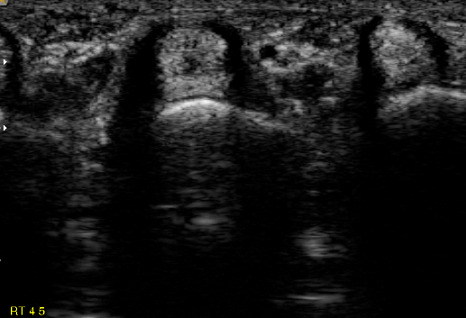

수술은 국소 마취하에 초음파를 보고 위치를 확인하여 활차절개술을 시행하며,